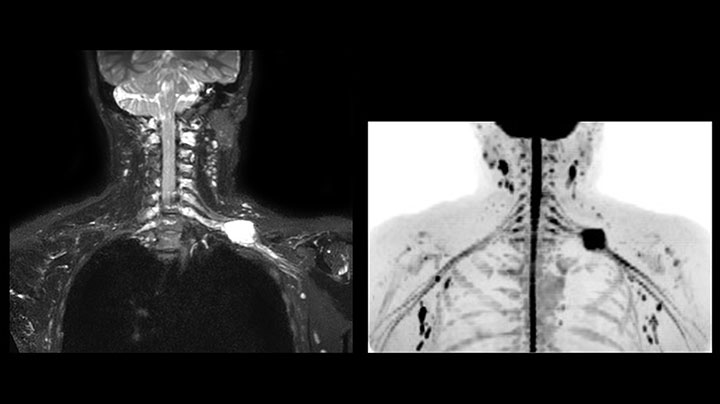

Obgleich die Region zwischen Hals und oberer Lungenspitze für ein MR-System einer der schwierigsten Bereiche ist, ergeben die mit Prodiva 1.5T erfassten Bilder bei diesem 56-jährigen Mann mit einem Pancoast-Tumor rechts eine gute Qualität. mDIXON TFE Bilder zeigen eine hervorragende Fettsuppression im Halsbereich und die diffusionsgewichtete Bildgebung enthält fast keine Verzerrungen.

Hier handelt es sich um eine 43-jährige Patientin mit einem supraklavikulären Nervenscheidentumor links. Die Läsion ist auf den STIR VISTA Bildern und auf der MR-Neurographie mit diffusionsgewichteter MRT gut zu erkennen. Die Untersuchung wurde mit Prodiva 1.5T durchgeführt.

Erfasste Voxelgröße: 1,2 x 1,3 x 2,4 mm, rekonstruierte Voxelgröße: 0,7 x 0,7 x 1,2 mm, dS SENSE Faktor: 2, Scandauer: 5:46 Minuten.